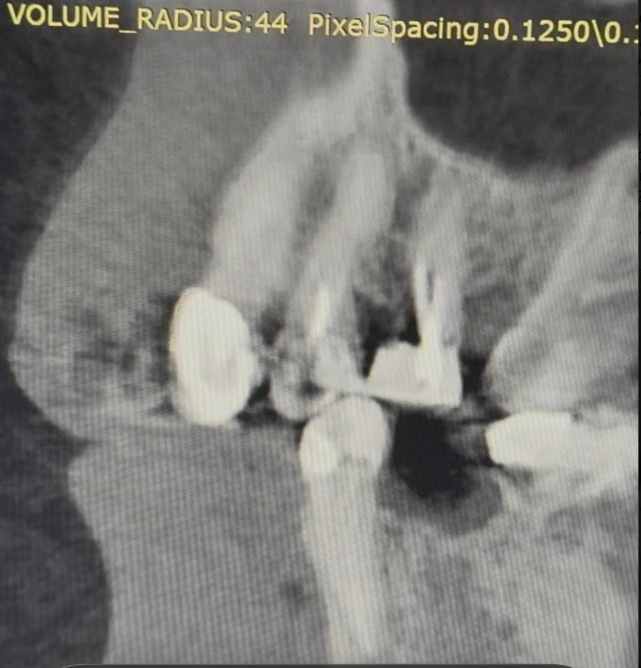

Добрый вечер Подскажите пожалуйста, вчера ел арахис, это очень редко бывает и мне такое противопоказано, и слышу один твёрдый попался немного, в момент когда накусил немного в области 4–5 зуба вверху справа, почувствовал боль, которая по сейчас сохраняется, боль чувствую именно в периодонте (к сожалению кто меня помнит с моей историей длительной я уже знаю как отличать боль по чувствительности, ту или иную), делал КЛКТ 3 недели, просто планово по поводу других зубов, посмотреть что и далее сохраняется положительная динамика после больших перенесённых периодонтитов, в вот посмотрел заодно на вот эти (открыл дайком) где вчера накусил, там нет и не было деструкции кости, зубы давно мертвые и нужно менять реставрации, зубы эти при надавливании пальцем не болят, жевать тоже не усиливается, просто ноющая периодонтальная боль извините за сленг, острой боли прям в момент накусывания арахиса тоже не было

Предполагаю что это возможно травматический периодонтит, если так, то какова тактика ?

Рентген сегодня сделал, трещины нет, но я слышал не на рентгене не на клкт часто трещины не видны, и лишь только под микроскопом